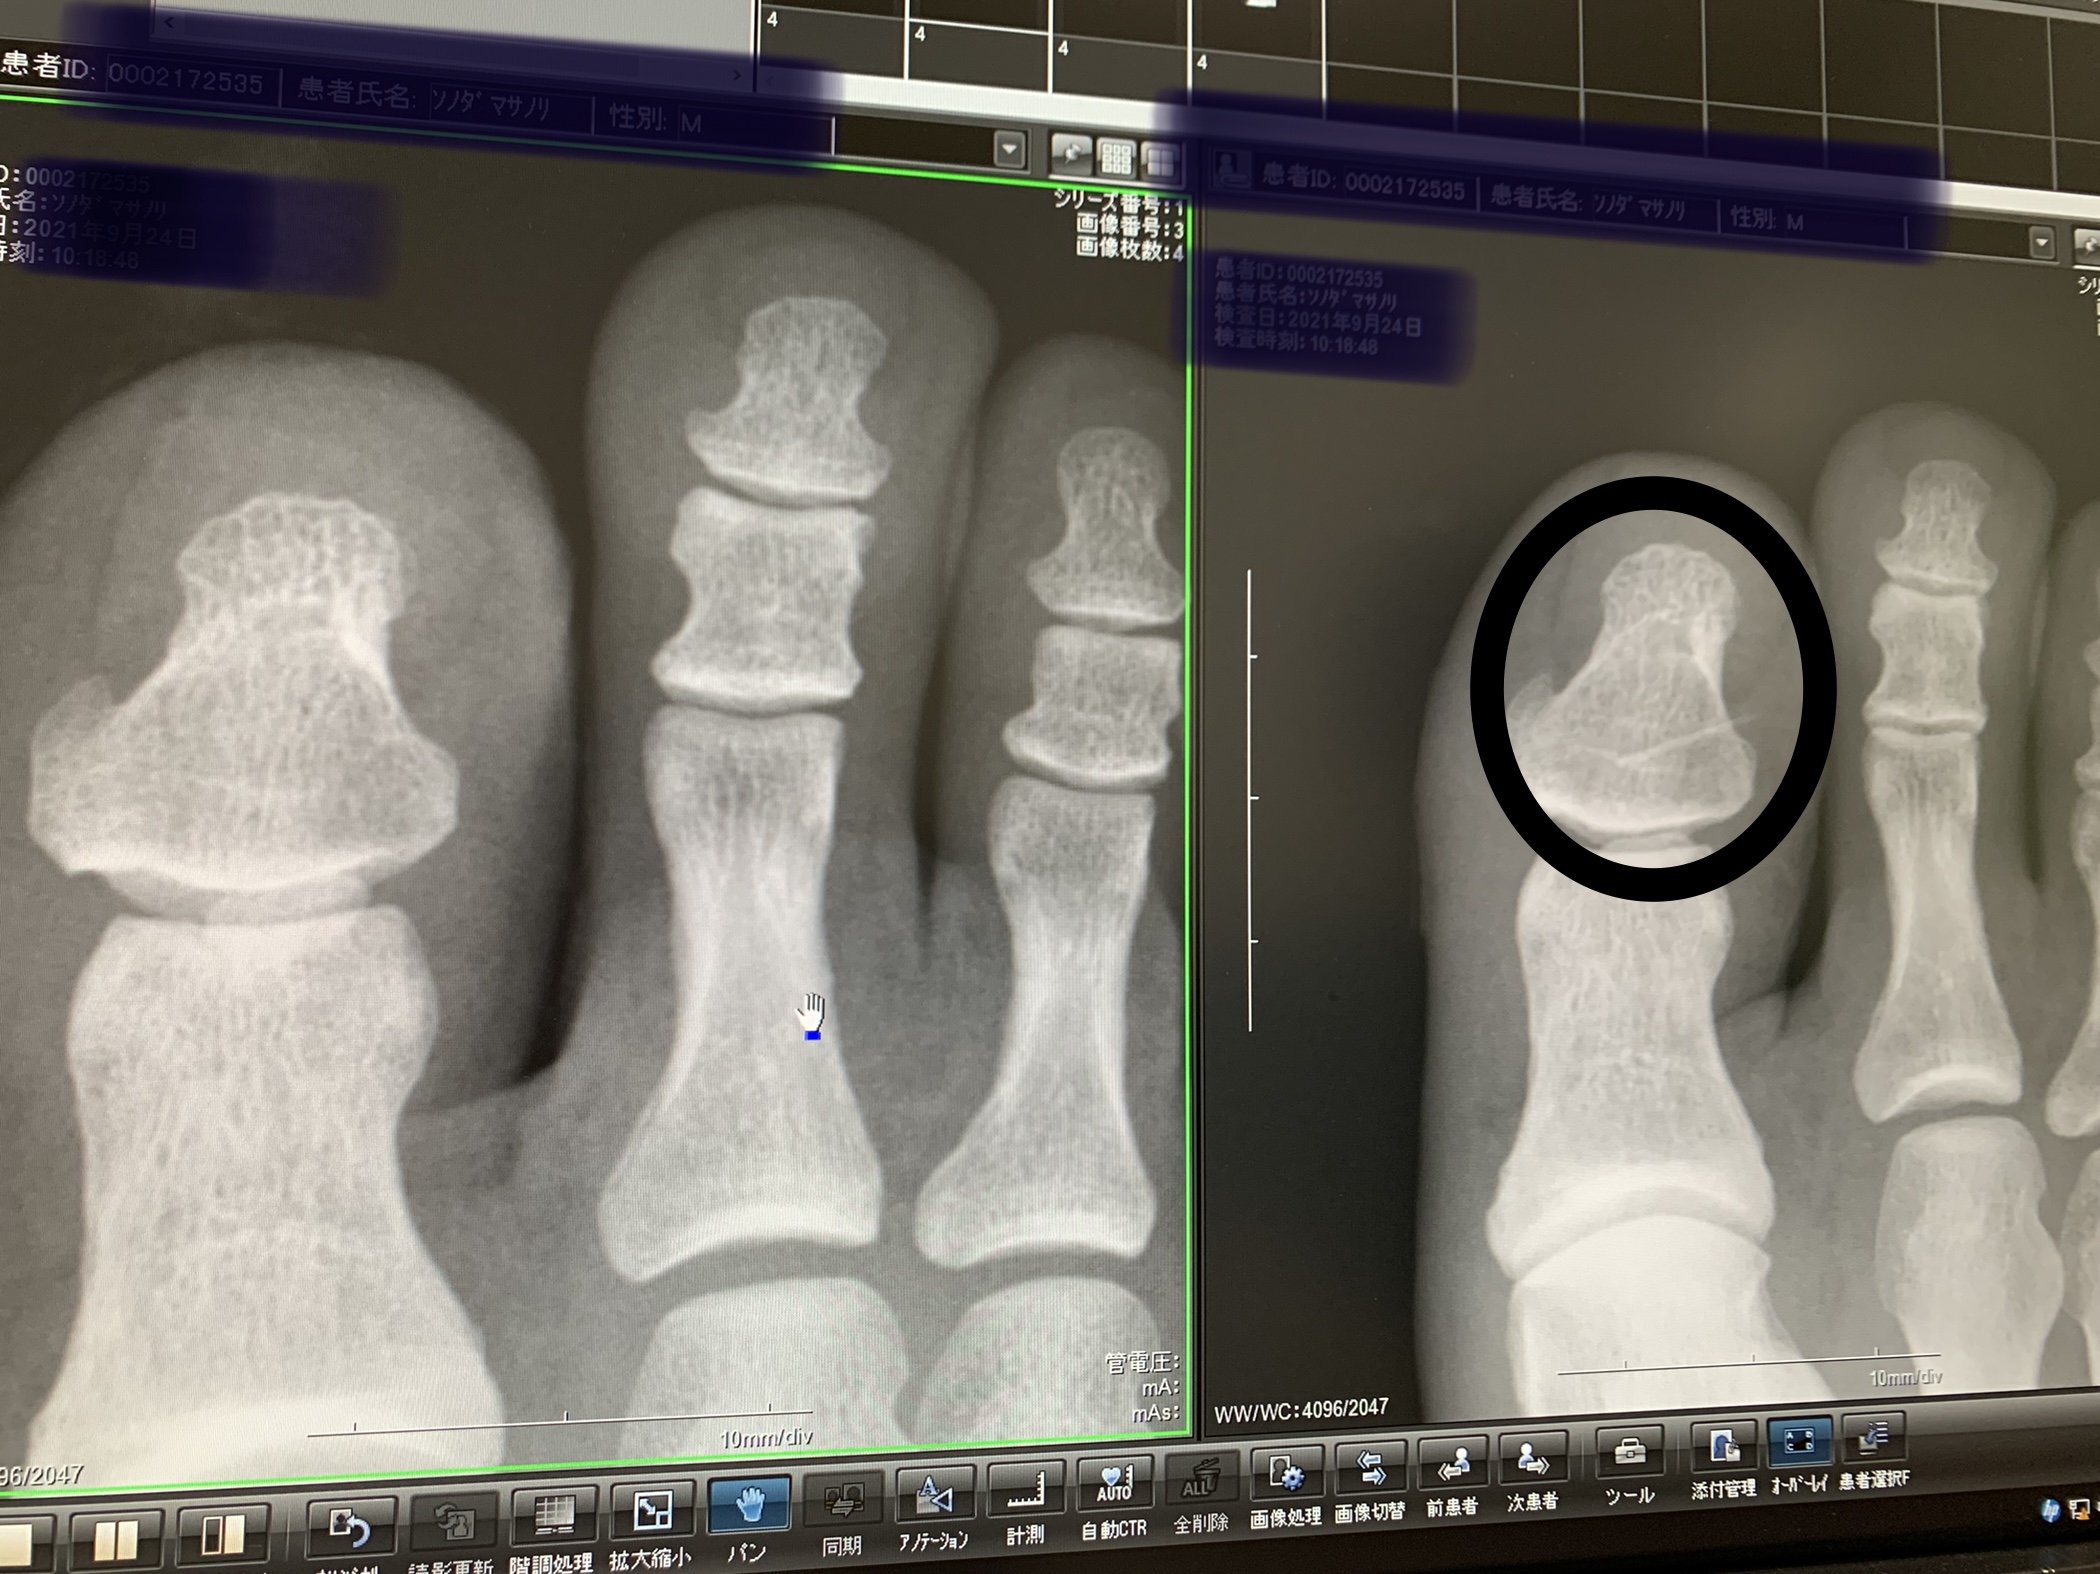

足元をビーチサンダルで行っていた事が最大の功罪だったんですが😢😢😢、吊り上げた真鯛が最後の足掻きでドタバタしているときに当方の右足指に剣先がぐさりっと😢😢😢…自宅にかえってピンセットで取ろうとしてもなかなかの大きくて抜けず…次の日に病院で抜いて頂きました。グサッとつきっさった鯛の最後の反撃、しっかりと噛みしめてまたの釣行に生かします(笑)😖😖😖